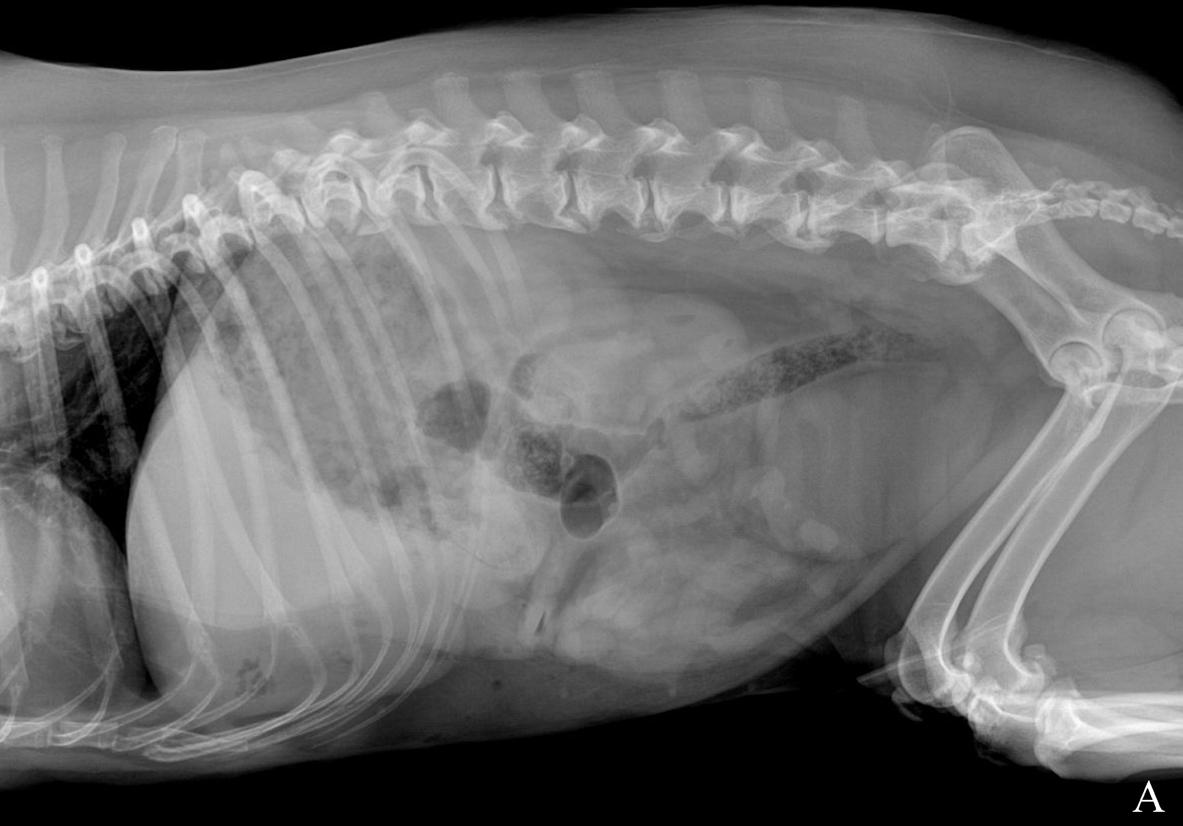

Se realizó un estudio radiográfico de abdomen con proyecciones lateral izquierda y ventrodorsal (Fig. 1).

Figura 1. Radiografías de abdomen de un perro mestizo de 12 años en proyección lateral izquierda (A) y proyección ventrodorsal (B).

Describe las alteraciones radiográficas observadas

Se observa una disminución de la visualización de las serosas abdominales en el abdomen craneal y medio (Fig. 2), con presencia de pequeñas burbujas de gas libre caudoventral a la silueta hepática compatible con neumoperitoneo (Fig. 2A). Ambas proyecciones mostraban una hepatomegalia con bordes redondeados excediendo levemente el arco costal, con presencia de una zona de opacidad gas, de morfología y bordes irregulares, poco definidos, localizada en la zona de proyección hepática en su aspecto craneoventral y con lateralización hacia la derecha (Fig. 2). Así mismo, se apreció otra lesión, de opacidad gas y de menor tamaño, caudalmente a la previamente descrita, en la zona media del hígado y asociada a un efecto masa en la proyección ventrodorsal, que producía hacia caudal un desplazamiento del cuerpo gástrico y antro pilórico (Fig. 2B). Como hallazgo incidental, se observó una espondilosis ventrolateral deformante en la columna lumbar.

¿Cuáles son los diagnósticos diferenciales compatibles con los signos radiográficos observados?

La pérdida de diferenciación de serosas fue compatible con un leve volumen de líquido libre abdominal o inflamación peritoneal, sin poder descartar otras causas como una carcinomatosis/sarcomatosis peritoneal. Las causas más comunes de neumoperitoneo incluyen heridas penetrantes, fuga de gas de órganos enfisematosos, perforación o rotura de órganos que contienen gas debido a traumatismos, neoplasias o ulceraciones y por causas iatrogénicas, (p. ej., laparotomías).1 La lesión localizada en la proyección hepática más cranealmente y lateralizada hacia la derecha con contenido gas, según su localización, podría ser compatible con un absceso hepático, colecistitis enfisematosa, neoplasia o granuloma hepático infectado. La lesión localizada más caudalmente y con efecto masa a nivel gástrico podría corresponderse con otro absceso o con la presencia de una masa necrosada de origen benigno (p. ej., hiperplasia nodular, quiste, hematoma) o maligno (p. ej., carcinoma hepatocelular).

Ante el conjunto de los hallazgos radiológicos encontrados, la sospecha principal fue de una rotura de un absceso/neoplasia hepática necrosada.

Figura 2. Imágenes ampliadas de las radiografías en proyección lateral izquierda (A) y ventrodorsal (B). Se observa la lesión de opacidad gas y bordes irregulares localizada en la proyección hepática, en su aspecto craneoventral y lateralizada a la derecha (flechas blancas). Se muestra otra lesión de opacidad gas, de menor tamaño respecto a la descrita, en la zona media del hígado (flechas moradas), que provoca un efecto masa (*) y genera un desplazamiento hacia caudal del antro pilórico y cuerpo gástrico (flechas negras). Caudoventral a la silueta hepática se observan pequeñas burbujas de gas libre compatible con neumoperitoneo (flechas azules).